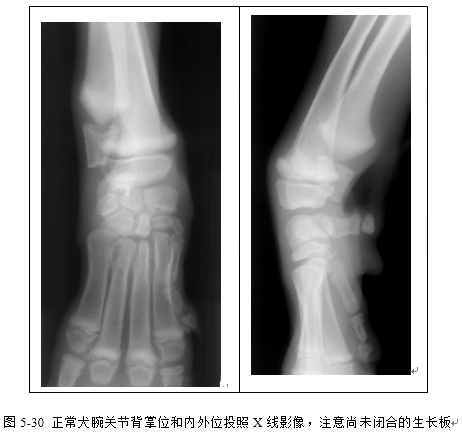

(2)识别桡尺骨、肱骨、肘关节、腕关节、肩关节X线影像(图5-28、5-29、5-30、5-31)。

(三)骺板(生长板)为位于骨骺和干骺端之间的软骨,X线片上显示为一低密度的带状阴影。骺板随年龄增长而闭合,但不同部位的骺板闭合时间不同。